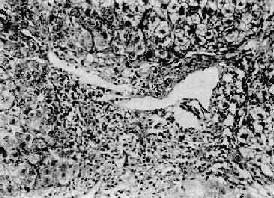

图10-39 肝细胞内的乙型肝炎表面抗原 免疫酶标法(双PAP)染色显示肝细胞浆内的HBsAg 3.重量病毒性肝炎本型病情严重。根据起病急缓及病变程度,可分为急性重型和亚急性重型二种。 (1)急性重型肝炎:少见。起病急,病变发展迅猛、剧烈,病死率高。临床上又称为暴发型、电击型或恶性型肝炎。 本型病变可见肝细胞坏死严重而广泛。肝索解离,肝细胞溶解,出现弥漫性的大片坏死。坏死多自小叶中央开始,向四周扩延,仅小叶周边部残留少数变性的肝细胞。肝窦明显扩张充血并出血,Kupffer细胞增生肥大,并吞噬细胞碎屑及色素。小叶内及汇管区有淋巴细胞和巨噬细胞为主的炎性细胞浸润(图10-40)。残留的肝细胞再生现象不明显。肉眼观,肝体积显著缩小,尤以左叶为甚,重量减至600~800g,质地柔软,表面被膜皱缩(图10-41)。切面呈黄色或红褐色,有的区域呈红黄相间的斑纹状,故又称急性黄色肝萎缩或急性红色肝萎缩。

图10-40 急性重型肝炎 肝细胞大片坏死消失,小叶中心部最重,周边部残存的肝细胞变性。坏死区有炎性细胞浸润